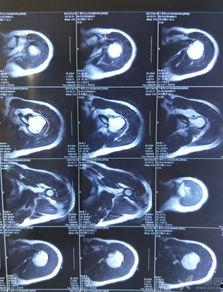

你有没有遇到过那种肩膀突然感觉不对劲,像是脱了臼但又没完全脱的情况?没错,说的就是肩关节半脱位!这种小麻烦虽然不常见,但一旦发生,真是让人疼得够呛。今天,就让我带你一探究竟,看看那些神奇的肩关节半脱位复位视频,它们是如何帮你轻松解决这个问题的!

首先,得先了解一下肩关节半脱位。简单来说,就是肩关节的骨头和关节盂之间发生了轻微的错位。这种情况可能是因为肩部受到外力撞击、过度拉伸或者姿势不当等原因造成的。虽然听起来有点吓人,但其实很多情况下,肩关节半脱位是可以自行恢复的。